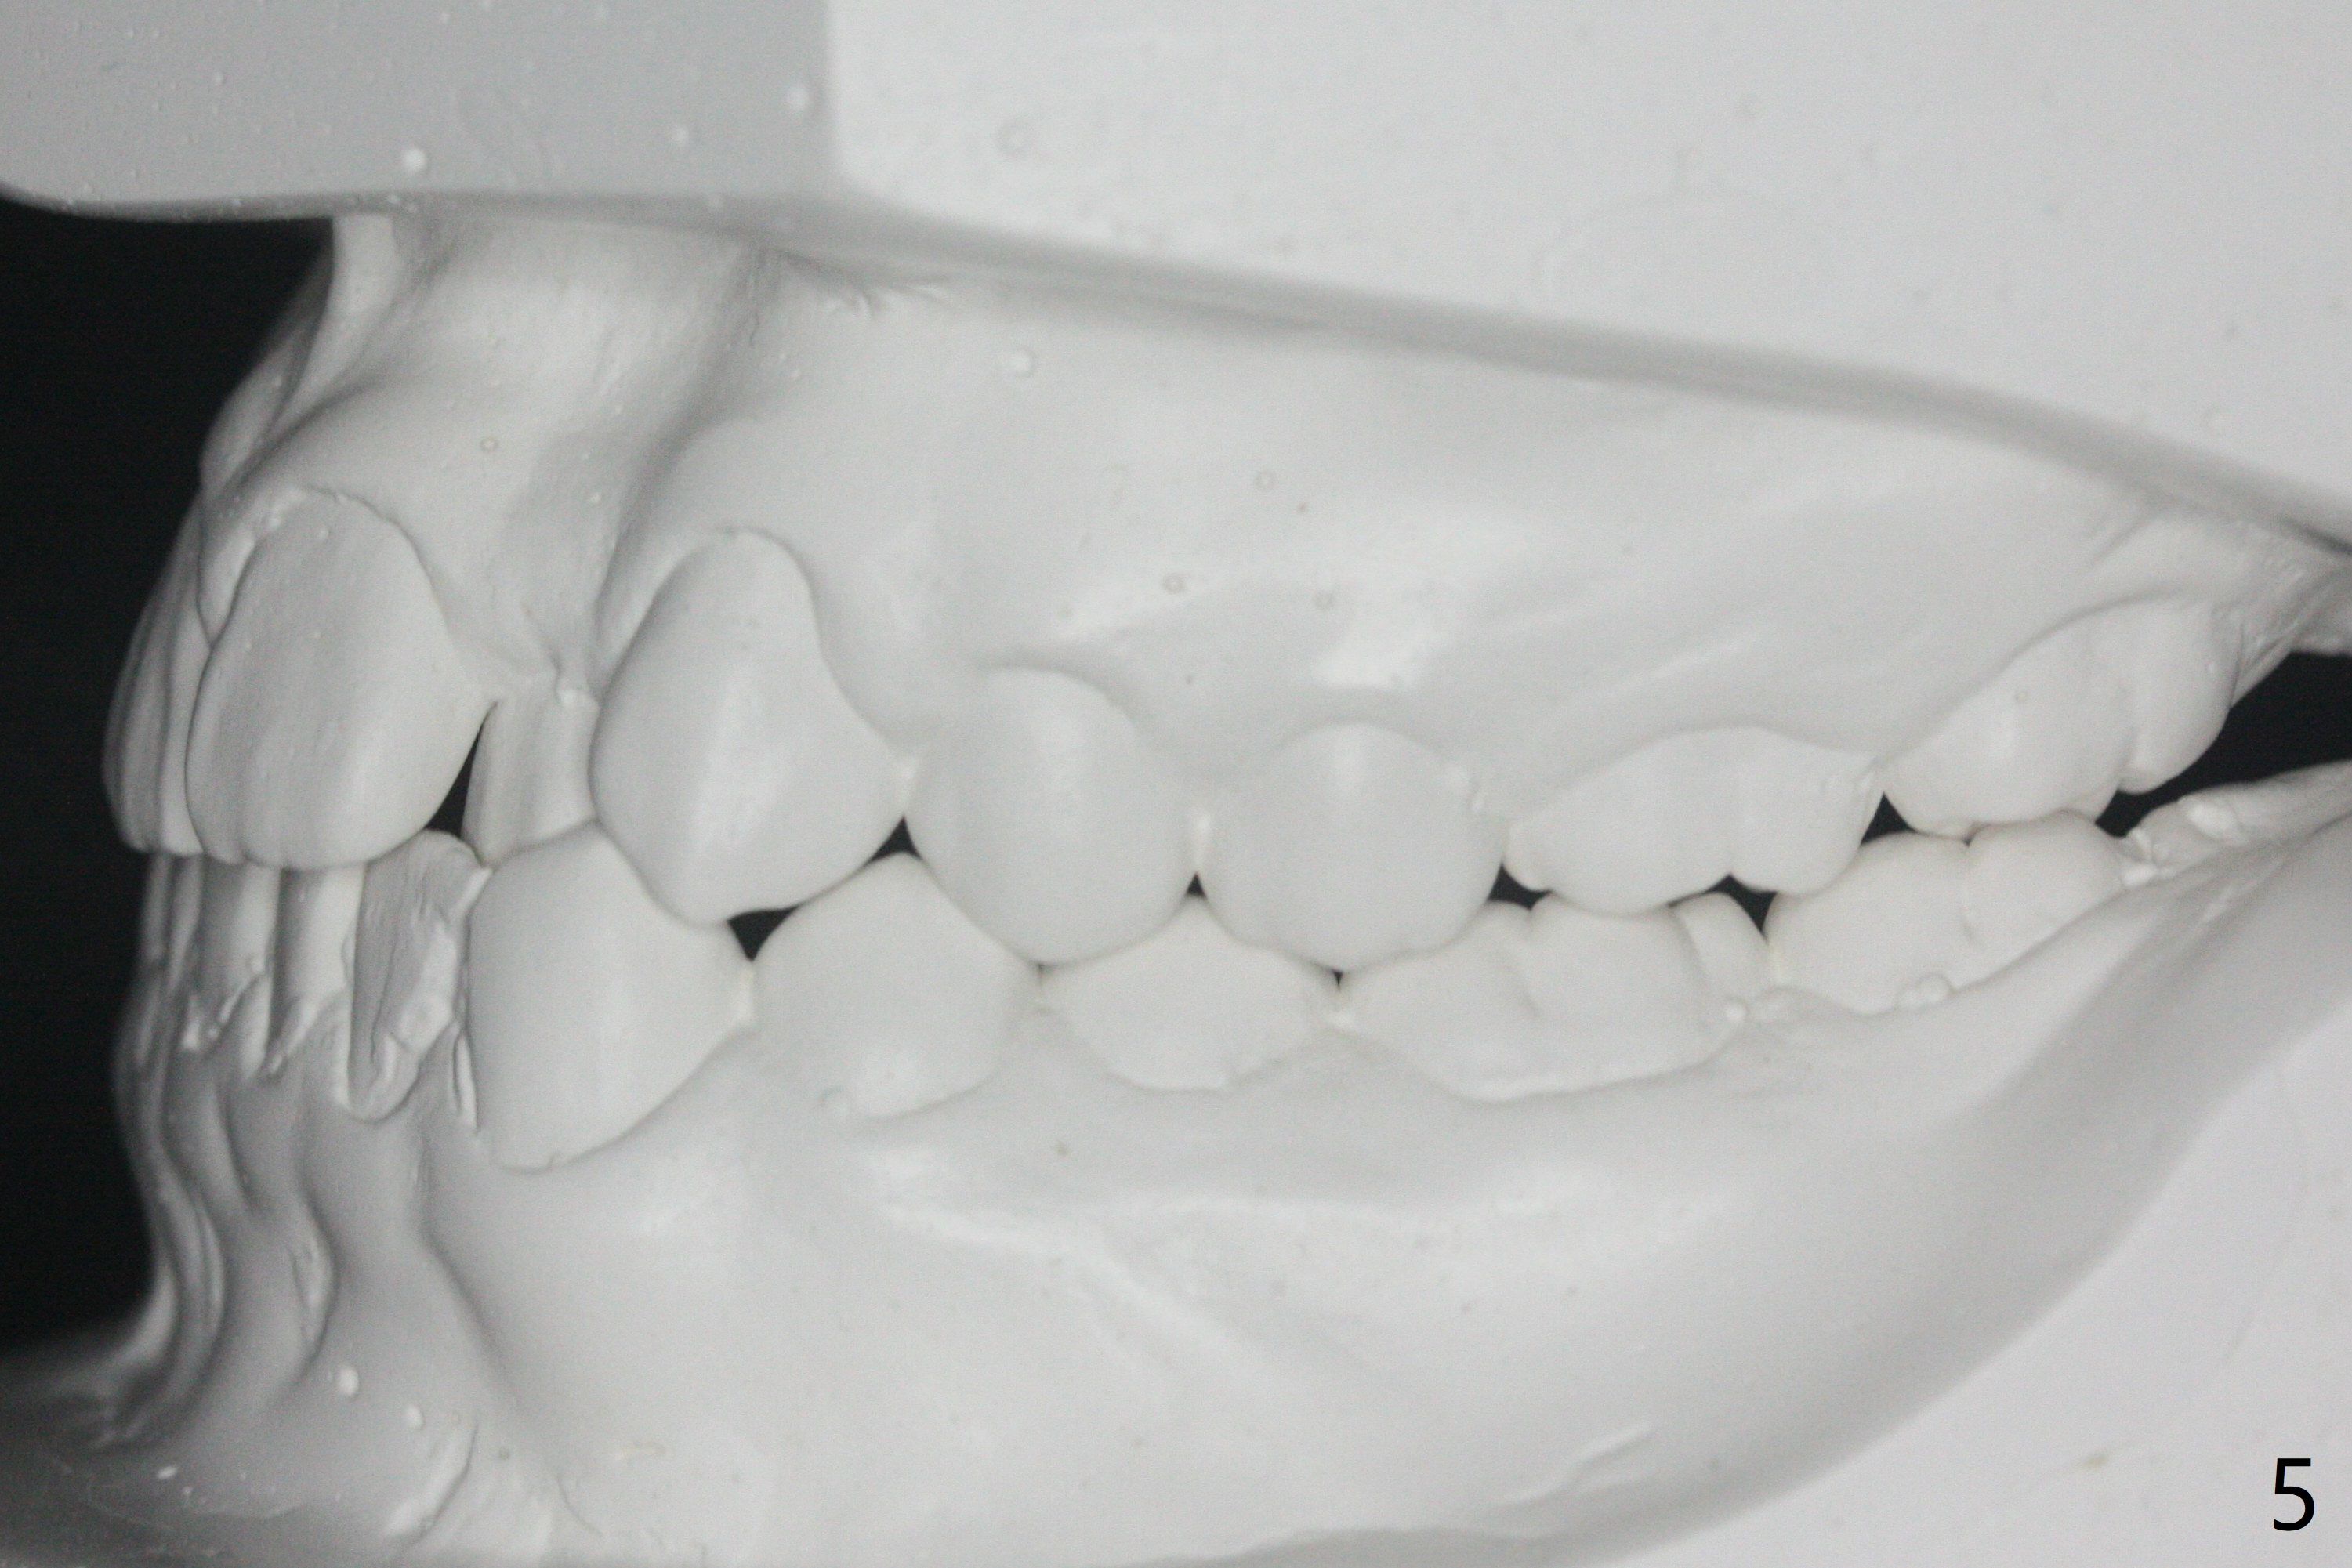

15岁男完成矫正1年9月,右侧后牙咬合理想(图二),上中切牙长轴改善,侧切牙torque不够完善(图四),左侧后牙咬合二类𬌗(图六,需要牵引),磨牙缝隙大(图八,十),造成食物堵塞,以后尽量避免使用磨牙bands,尤其是成人。